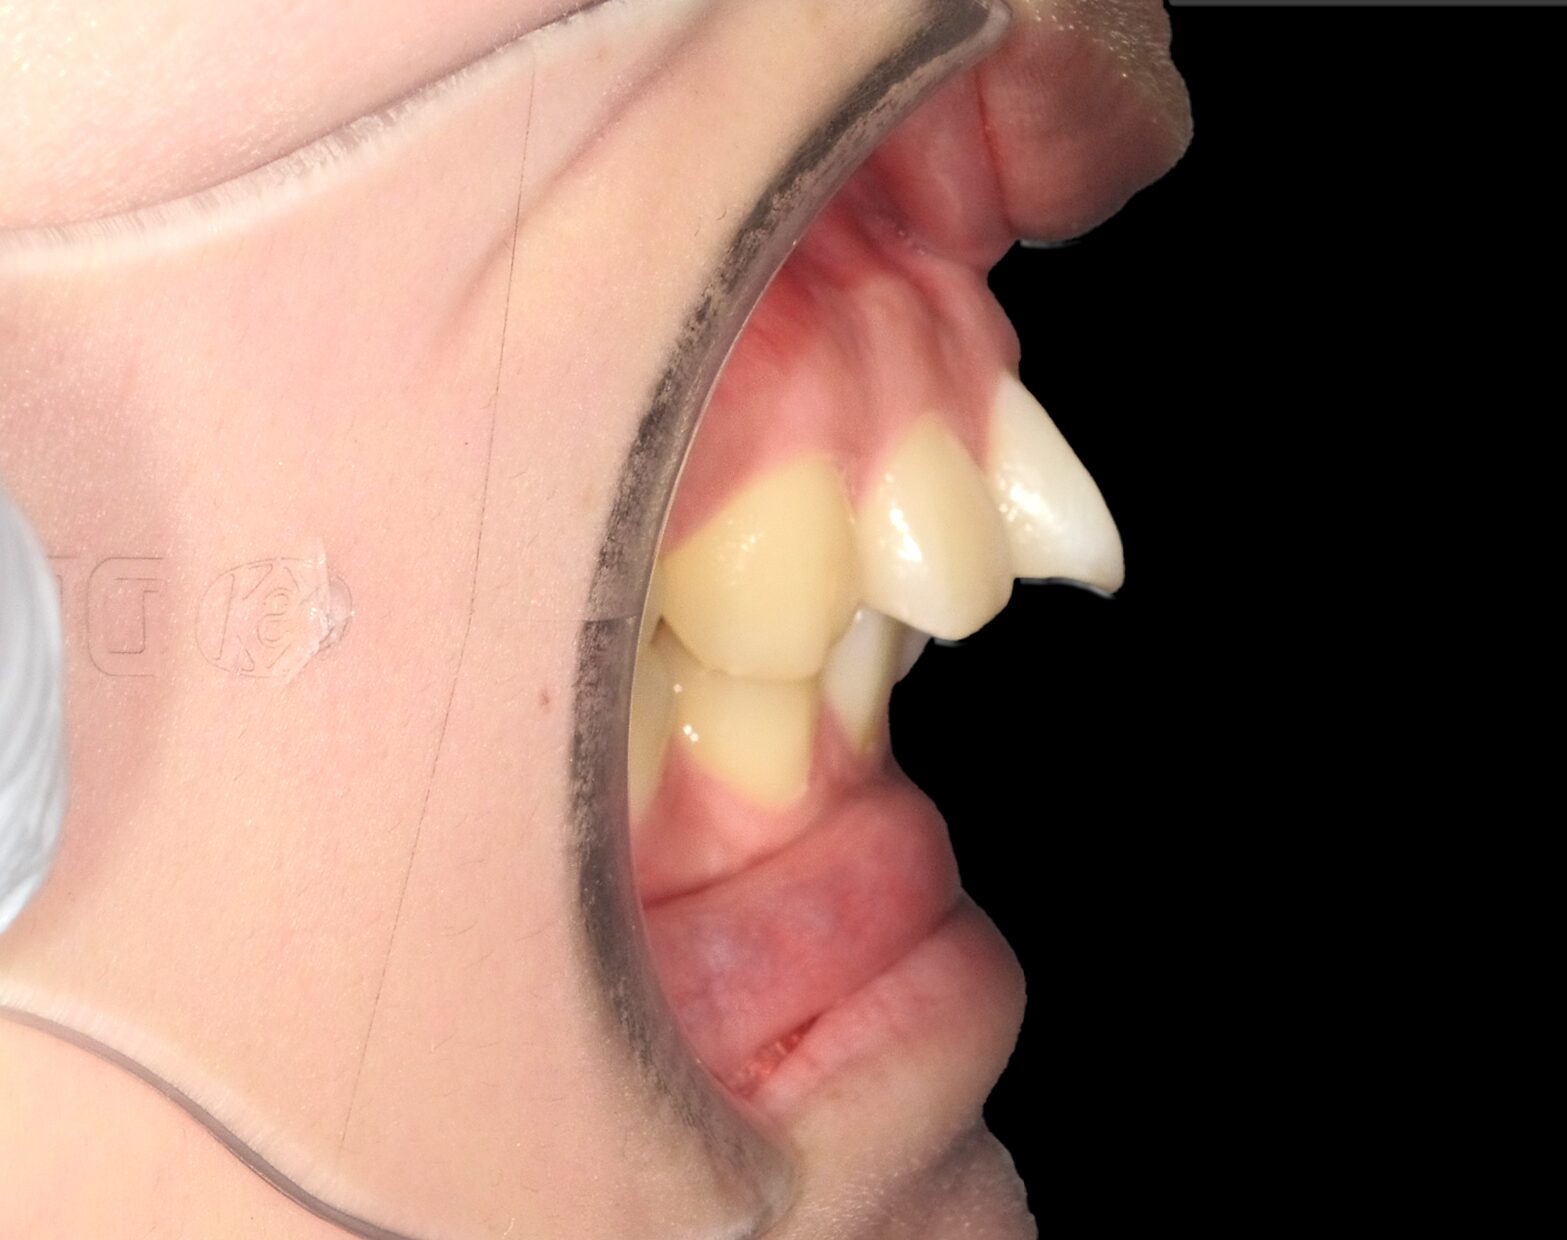

真横から見ると上の前歯が飛び出ています。

矯正治療にてこちらを綺麗に並べていきましょう。

真横から見ると、前歯が内側に位置し、出っ歯が改善しています。